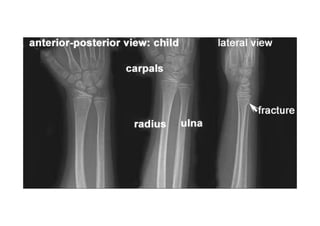

RADIOLOGIA DO

TRAUMA DO ESQUELETO

Referência: http://www.accessexcellence.org/RC/VL/